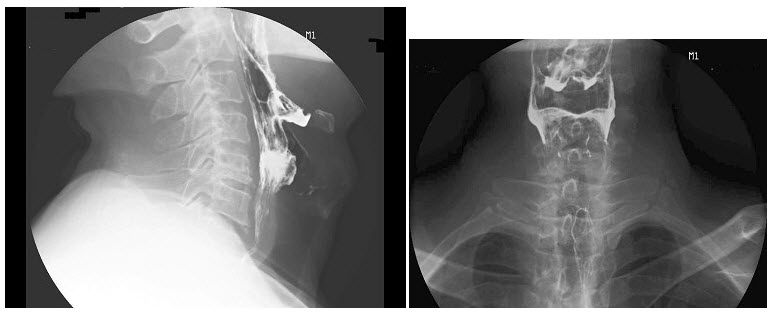

D.锁骨下静脉

E.降主动脉